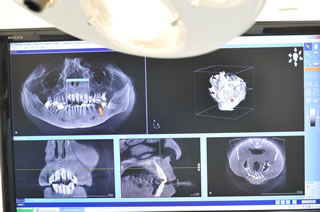

当センターでは、インプラント治療を診療に導入して以来、困難なケースやインプラントを行ったはいいが、その後の経過が思わしくないリカバリーを、他の静岡のインプラント専門歯科医や、学術集団と共に協力して解決してきた絶対的な自信があります。 我々は、同じ静岡市にある高度なインプラント専門医療機関と相互に技術提携もしています。 現在では3Dコンピュータによるシュミレーションされた技術により、ほとんどの方が安心して予定したインプラント治療を受けることができるようになっています。

インプラントが骨と一体化することが分かった頃のインプラント治療から、飛躍的な進歩をとげ、あごの骨の再生治療が確立した現在のインプラント治療は、専門的な知識や技術に特化した歯科医や技工士が互いに連携しあい、あらかじめ、どのような歯や噛みあわせになるか3Dコンピュータにより正確に予測し、理想的なインプラント治療を受けることができるようになっています。

また、患者さんは自分の望むインプラント治療の全体像の把握や、最終的にできる歯の形や噛み合わせの状態まで予想できるので、希望に沿ったレベルの高いインプラント治療が、普通に提供できるようになりました。